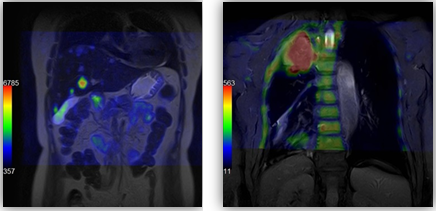

Результат – скорочення часу дослідження

Повний набір опцій для онкологічної візуалізації. Зокрема дифузійні зображення тіла і розрахункові високі показники b-фактора. Завжди висока, і незалежна від зовнішніх факторів і оператора, достовірність результатів. Чітка прив’язка існуючих дифузійно-зважених і зображень перфузії до конкретних анатомічних структур.